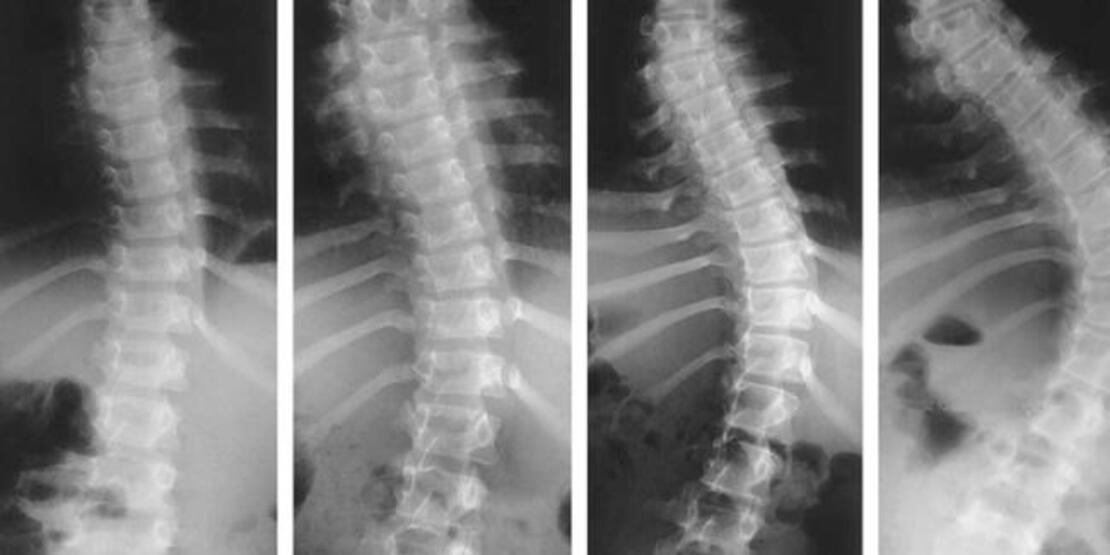

Ameliyat sürecine geri dönmek gerekirse, tüm çabalarımıza rağmen skolyozumun derecesi kontrol altına alınamadığı için diğer hastalara nispeten daha ilerlemiş bir derece ile daha zor bir müdahale geçirmek zorunda kaldım. Bu noktada tekrar belirtmek isterim ki, bahsettiklerim tamamen benim tedavi sürecime ilişkin durumlar. Her hastanın eğriliği, vücudu ve tedavi süreçleri birbirinden ayrı şekilde değerlendirilir. Örneğin 20 derecenin altındaki eğriliklerde hasta yakından izlenir. Aynı zamanda sırt ve bel egzersizleri ile yüzme önerilir. Herhangi bir korse tedavisi ya da cerrahi müdahaleye gerek duyulmaz. Skolyoz derecesi 20-40 derece arasında ve büyüme potansiyeli olan kişilerde korse tedavisi tercih edilebilir. Skolyozun derecesi 40 dereceden fazlaysa ise skolyoza cerrahi müdahale durumu gündeme gelir. Ancak burada önemli olan skolyozun ilerleme potansiyeli ve büyümenin durmuş olup olmadığıdır. Tedavi süreçleri bu iki duruma göre çizilir. Örneğin 8 yaşında, 30 derece eğriliği olan çocuğun tedavisi ile 18 yaşında, 30 derece eğriliği olan gencin tedavisi farklıdır. Çocuk ne kadar küçük olursa, eğriliğin ilerleme potansiyeli o kadar yüksek seyreder. Büyüme çağındaki bir çocukta sırttaki eğrilik 40 derecenin üzerine çıkmışsa beldeki eğrilik 35 derecenin üzerine çıkmışsa bu çocuklarda mutlaka ameliyat önerilir.2

Bahsettiğim tarihlerde büyüme çağında bir çocuk olarak sırtımdaki eğrilik 35 derece civarıyken belimdeki 50 derecenin üzerine çıkmış hatta 60 dereceye yaklaşmıştı. Bu nedenle cerrahi müdahale kaçınılmaz ve ertelenemez bir tedavi olarak karşımıza çıktı. Ameliyat süreci de hastadan hastaya değişiklik göstermesine rağmen, benim açımdan çok zor geçti. Başka hasta hikayeleri okuduğunuzda eminim bu süreci çok rahat atlatan ve kısa sürede günlük hayatına dönen insanların hikayelerine de denk gelebilirsiniz ancak benim hikayemde öyle olmadı. Eğriliğin derecesi arttığı gibi ameliyatın riskleri de arttı. Özellikle ailem, ameliyat evraklarını imzalarken her sayfada ciddi bir felç riski ile karşı karşıya olduğumuz gerçeğiyle yüzleşmek zorunda kaldı.